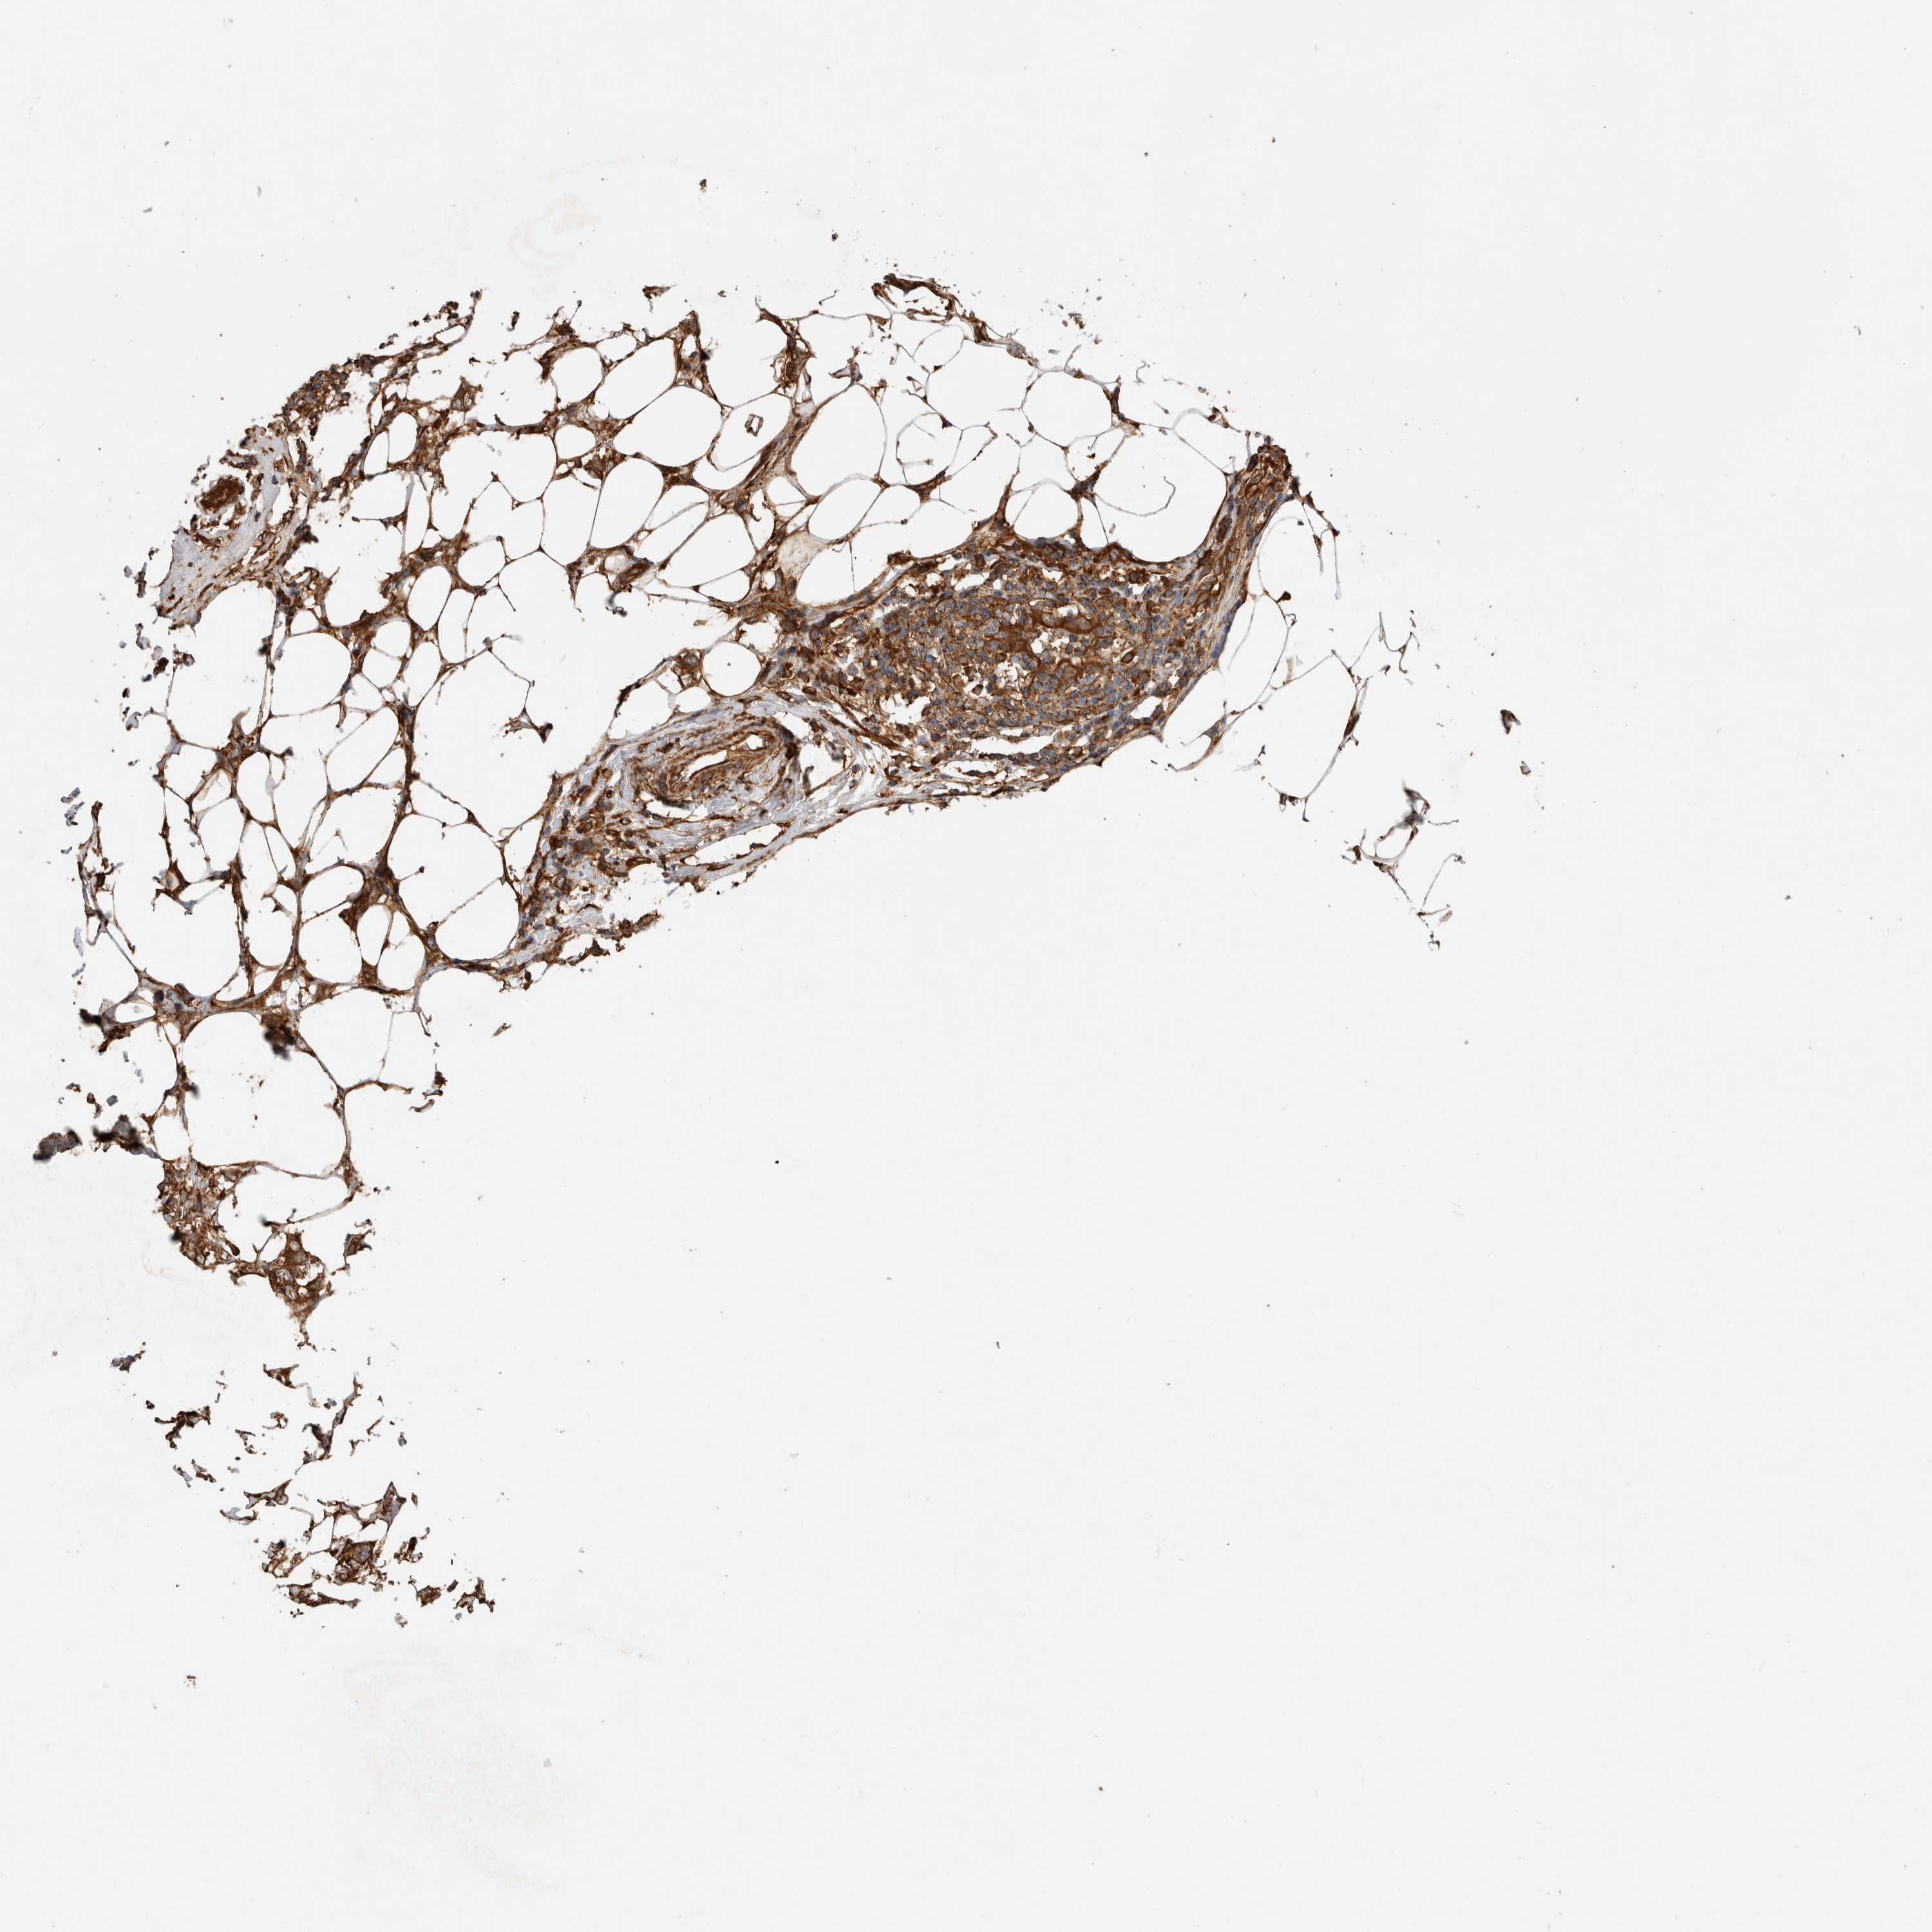

CANCER BREAST CANCER Show tissue menu

BRCA TCGA BRCA VALIDATION PROTEIN EXPRESSION